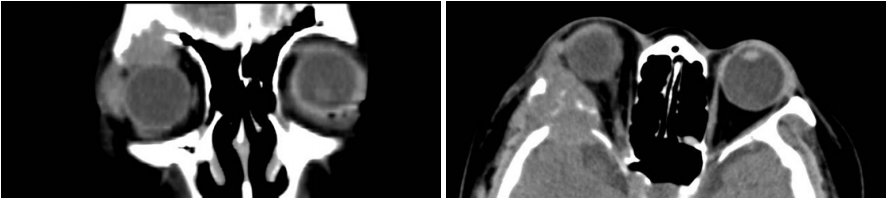

3例脉络膜转移性CC-RCC均为男性,例1和例3均为62岁,例2为51岁,平均58岁,均表现为右眼前黑影伴视力下降,病程分别为6月,1月和4月。术前检查视力均为右眼前手动,右眼底见视网膜下隆起肿块伴视网膜脱离。3例B超均显示右眼球内隆起肿物,例1和例2位于后极部,例3位于鼻侧球壁,中等回声,大小7.1~8.4 mm × 15.5~18.2 mm,均伴表面视网膜脱离,例3伴挖空征及脉络膜凹陷征,考虑脉络膜黑色素瘤(图1 )。例2两年前行左肾癌手术,1年前右肺上叶转移,术前胸部C T显示双肺多发结节,右侧为著,大者2 cm ×2 cm。例1术前胸部CT显示两肺内多个小结节影,大部分位于两肺外带,结节边界尚清晰,符合肺转移瘤表现。3例均在我院眼科全身麻醉下进行了右眼球摘除及义眼座的植入(表1)。

图1 右眼脉络膜转移性CC-RCC患者(例3):B超检查示右眼鼻侧球壁前探及8.4 mm ×15.53 mm半球形中高回声,伴挖空征及脉络膜凹陷征,考虑脉络膜黑色素瘤

Figure 1 Choroidal metastatic CC-RCC (case 3): B-scan ultrasound demonstrated an intraocular mass with medium to high internal reflectivity suspected of choroidal melanoma